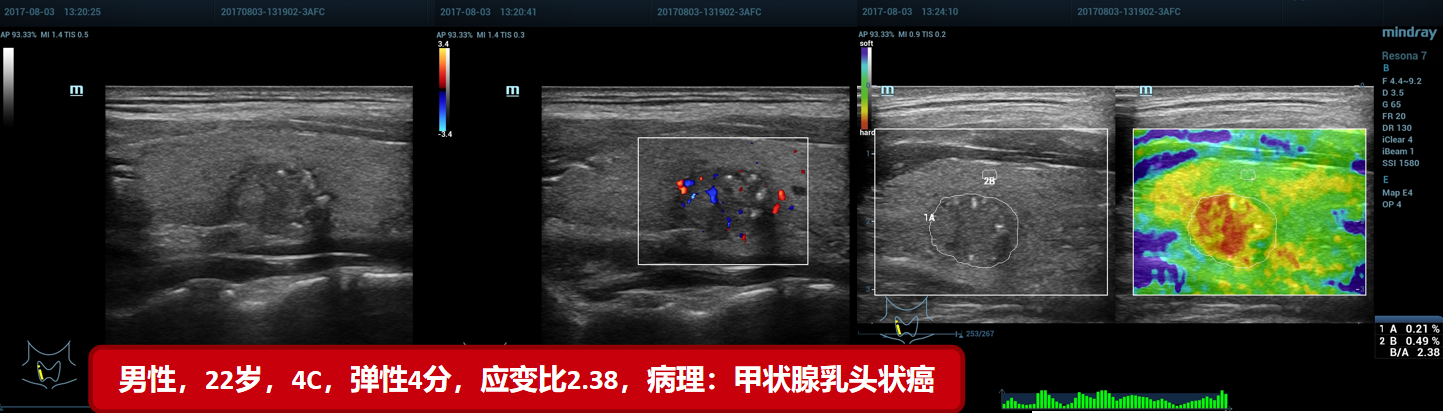

5、甲状腺乳头状癌(贵州医科大附属医院)

5、甲状腺乳头状癌(贵州医科大附属医院)